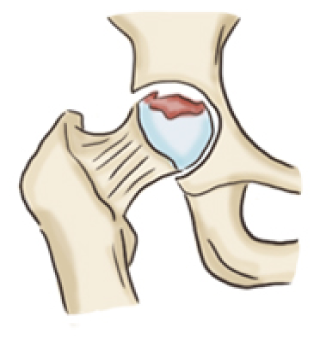

대퇴골두에 혈류가 차단되면 뼈조직이 죽는 괴사가 일어나는데 이를 '대퇴 골두 무혈성 괴사'라고 진단합니다.

흔히 뼈가 썩는다라고 알고 있는데 뼈가 썩는 것이 아닌 조직이 죽어 골절되거나 무너져 내리기 쉬운 상태를 뜻합니다.